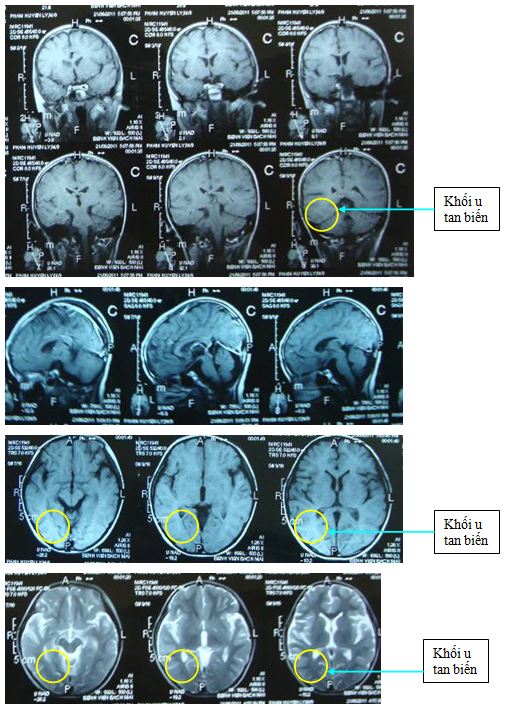

Trên phim chụp cộng hưởng từ sọ não sau xạ trị: khối tổn thương u đã tan biến.

Đây là một trong những trường hợp u não ở trẻ em được điều trị thành công tại Trung Tâm y học hạt nhân và Ung bướu Bệnh viện Bạch Mai.